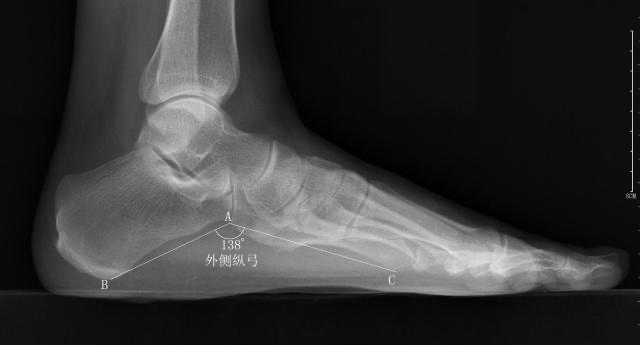

外侧纵弓

-

正常值:130°~150°

测量方法:从跟骨最低点到跟骰关节最低点作一条直线,再从跟骰关节最低点到第5跖骨头最低点作一条直线,然后测量两条直线构成的夹角

扁平足时外弓角增大,弓形足时相反